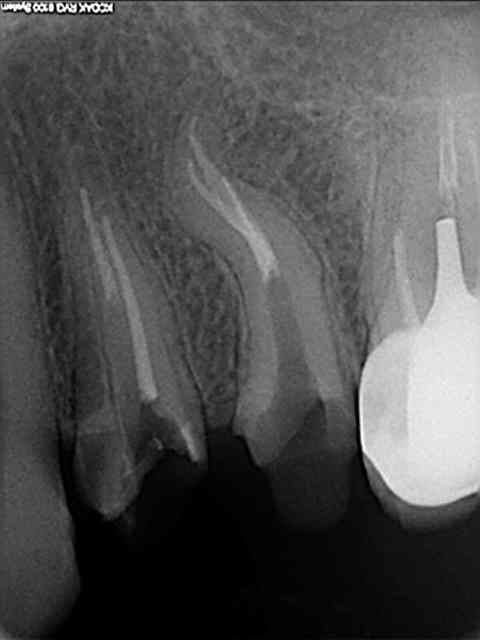

Voici un cas de fracture compacteur.

Utiliser un mac spaden dans ce genre de cas était une bêtise.

Aprés beaucoup d'efforts pour perméabliser les 2 cannaux et les préparer, c'est trop dommage de gacher le résultat en cassant un compacteur.

Cela ne m'a pas gêné pour desobturer et faire l'empreinte pour l'inlay-core, mais la condensation de la gutta au niveau apical n'a pas été terrible.

C'est d'ailleurs un des cas qui m' a décidé à utiliser de temps en temps le thermafill.